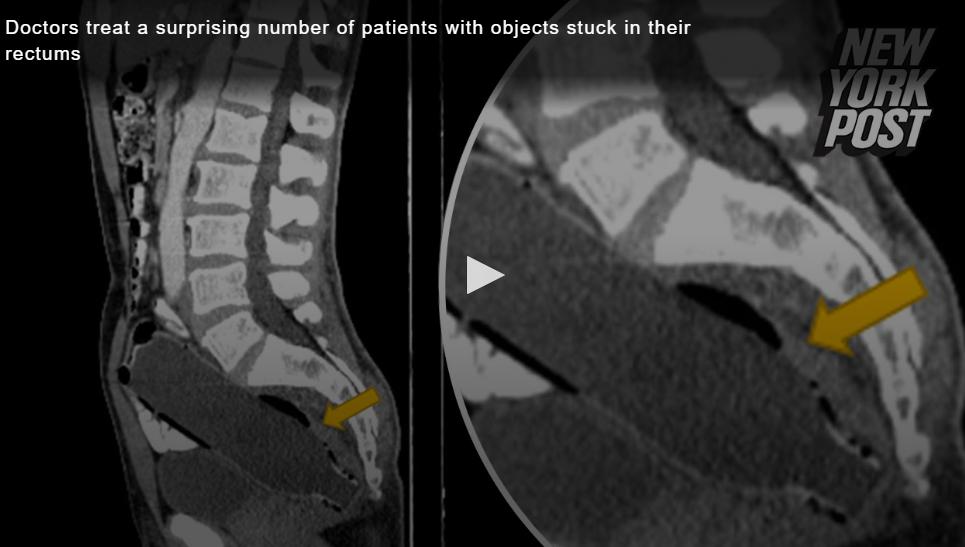

前不久,美国某肛肠科医生在自己的TikTok账号上分享了一连串离谱病例。

据他本人自述,在过去几十年的从业生涯中,曾在病人的直肠里掏出过仓鼠、菠萝、蜡烛等物品。

在视频里,Kenji医生表示自己作为芝加哥地区的肛肠专家,经常被问2个问题:你见过最恶心的病例是怎样,你从别人屁股里掏出最奇怪的东西是什么?

面对这些让人啼笑皆非的问题,Kenji表示他确实见过很多奇怪的病例,他们的病因总结起来就是四个字——肠道塞车。

Kenji介绍说,这些病人的平均年龄在40-45岁左右,男性占了近78%。除了少部分醉酒晕倒坐进去的病例外,其他大多数病人在就医时大多都提到,自己有几十年的便秘史,偶然得知“塞入式疗法”能让肠道变宽,方便排便???